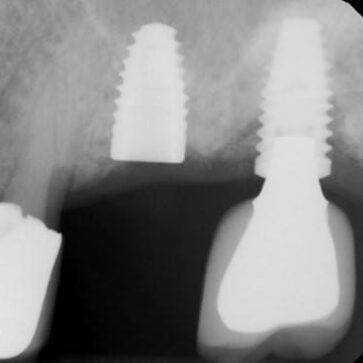

With the screw and implant threads hammered together, it was exceedingly difficult for the initial tap to find and engage the first “starting” thread fragment and “clock” into the existing implant threads to initiate cleaning or removing just screw thread pieces, without inappropriately engaging and removing an implant thread. Eventually, the tap overcame this problem and thread fragments were retrieved, but it was not without top implant thread damage, as it took several threads for the correct thread timing to be established with the tap. Following retrieval of the screw thread fragments, the implant was cleaned, thoroughly dried, and a polyvinyl impression was taken to assess the thread damage. As can be seen below, while there are remaining threads, the top threads had more damage as the thread clearing process improved as the tap found more existing implant threads.

Post retapping the implant to M1.8. Notice the substantially improved threads, even though the diameter increase is onle .1mm in radius. Also note, there are additional deep threads gained over the original predrill length, as there was no effort to deepen the predrill bore. This effort was made, as the first thread was not fully recovered by enlarging the diameter.